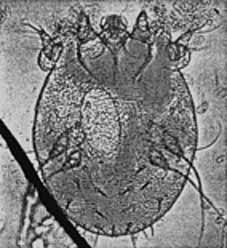

La SCABBIA [in antico si usava genericamente il termine ROGNA che attualmente è esteso solo al mondo animale ma ha grandi prossimità patologiche] è una malattia infettiva altamente contagiosa, l’agente causale è l’acaro (SARCOPTES SCABIEI).